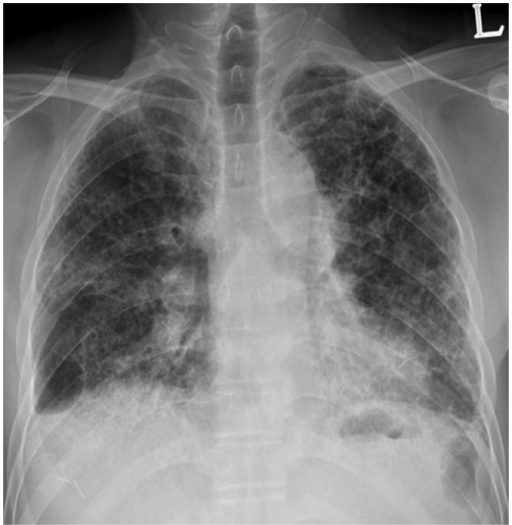

Puzzle 20

What's the Diagnosis?